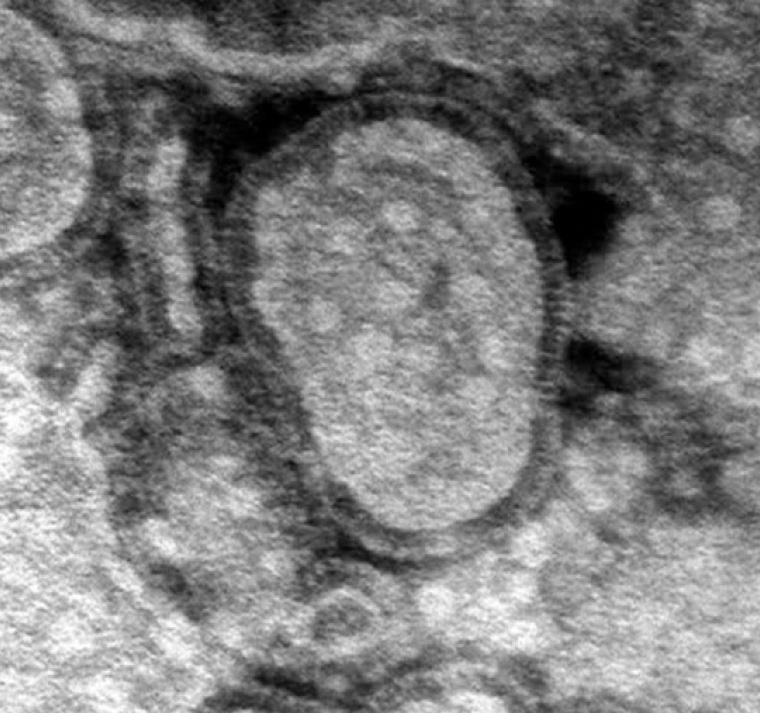

Cinco años después de la pandemia de Covid-19, China enfrenta un brote de metapneumovirus humano (HMPV), otra enfermedad respiratoria. Según informes y publicaciones en redes sociales, el virus se está propagando rápidamente y algunos afirman que los hospitales y crematorios están desbordados. Videos compartidos en línea muestran hospitales abarrotados, y algunos usuarios indican que múltiples virus, como la influenza A, el HMPV, Mycoplasma pneumoniae y Covid-19, están en circulación.

Se ha especulado que China ha declarado el estado de emergencia, aunque esta información no ha sido confirmada. Se sabe que el HMPV causa síntomas similares a los de la gripe y puede generar signos parecidos a los del Covid-19. Los funcionarios de salud están siguiendo de cerca la situación mientras el virus continúa propagándose.

Los casos recientes incluyen patógenos como el rinovirus y el metapneumovirus humano, con un aumento notable en los casos de HMPV entre niños menores de 14 años, especialmente en la región de Uttar Pradesh.